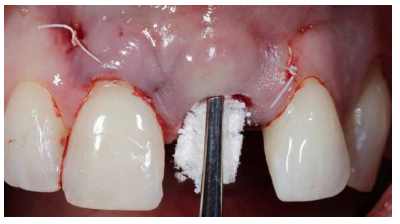

De forma posterior, con el fin de garantizar la estabilidad de los tejidos blandos y para lograr una anticipación a la remodelación de los tejidos duros que se traducirán en defectos vestibulares, se llevó a cabo una preservación ósea de la región vestibular del alveolo. Para ello, se utilizó un xenoinjerto óseo reforzado con colágeno (BioOss® Collagen, Geistlich) que se colocó en el gap entre la cortical vestibular y el propio implante. (Figura 15).